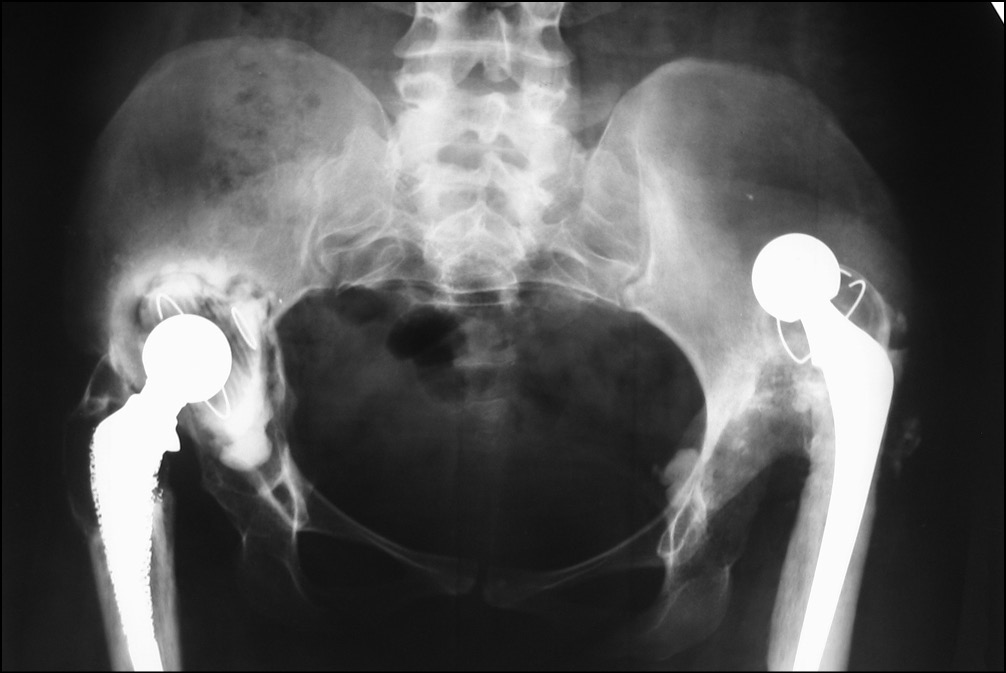

На контрольных рентгенограммах выявлен дефект вертлужной впадины типа IIIA и дефект бедренной кости типа IIIB по классификации W.G. Paprosky. В 2012 г. по поводу нестабильности тотального эндопротеза левого тазобедренного сустава выполнено ревизионное эндопротезирование с использованием антипротрузионного кольца ЭСИ (фирма Эндосервис) с цементной чашкой и бедренного компонента типа Цваймюллера, дефект бедренной кости восстановлен с применением свежезамороженного кортикального трансплантата. (рис. 7 и 8).

Рис. 7. Рентгенограмма таза перед ревизионным эндопротезированием левого тазобедренного сустава в 2012 г.

Рис. 8. Рентгенограмма таза после ревизионного эндопротезирования левого тазобедренного сустава в 2012 г.

В октябре 2019 г. пациентка обратилась на консультативный прием с жалобами на боли и ощущение нестабильности в правом тазобедренном суставе при незначительной физической нагрузке (рис. 9).

Рис. 9. Рентгенограмма таза при поступлении в клинику для ревизионного эндопротезирования правого тазобедренного сустава в 2019 г.

После выполнения обзорной рентгенографии таза с захватом тазобедренных суставов выявлена нестабильность тотального эндопротеза правого тазобедренного сустава: обширные сегментарные дефекты вокруг вертлужного компонента, миграцию вертлужного компонента медиально и краниально, резорбция костной ткани вокруг бедренного компонента в 1, 2, 6 и 7-й зонах Груена. Рентгенологически дефект вертлужной впадины был оценен как тип IIIB по классификации W.G. Paprosky (рис. 1).